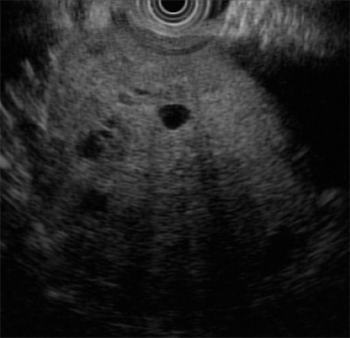

췌장의 낭종성 병변으로 판단하고 자세한 관찰과 필요한 경우 조직검사 혹은 세포흡인검사를 위하여 내시경초음파(EUS)를 시행하였다. 췌장 미부의 echogenic round mass가 관찰되었고 종괴 내부에는 다양한 크기의 낭성 병변이 동반되어 있었다. 낭내에는 격벽이나 벌집 (honeycomb) 양상, 석회나 벽결절 (mural nodule) 등은 관찰되지 않았다 (Fig. 2).

Figure 2. Round echogenic mass was noted on the tail of pancreas with multiple variable sized round small cystic lesions.